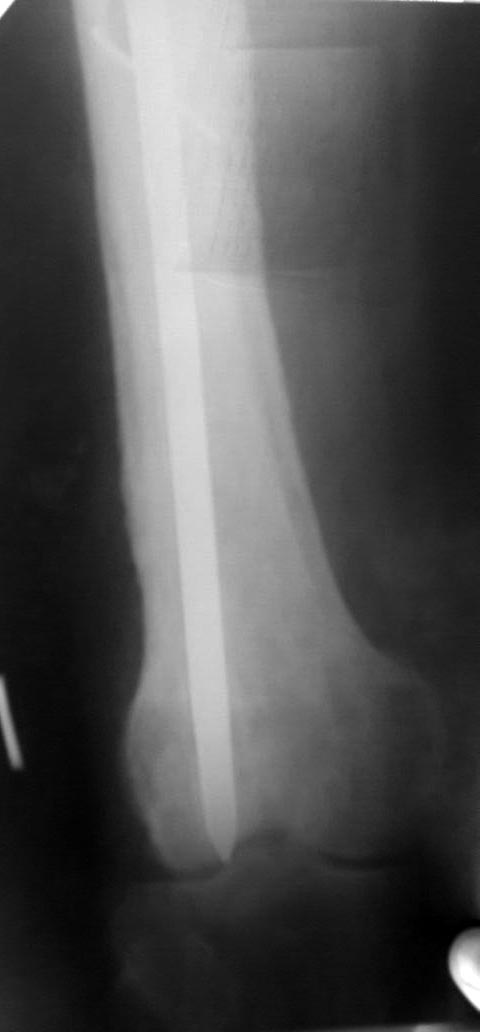

Доброго дня коллеги!поступает пациент, оперирован 9 лет назад,

последний месяц начали беспокоить боли в коленном суставе при ходьбе

последний месяц начали беспокоить боли в коленном суставе при

ходьбе!Визуально отек коленного сустава,синовит, ограничение и сгибания

и разгибания. наш план зайти антеградно при помощи эопа и всетаки

попытаться его удалить. Сейчас ищем инструмент через москву. на потоке

это никогда не ставили. хотелось бы услышать мнения, советы.